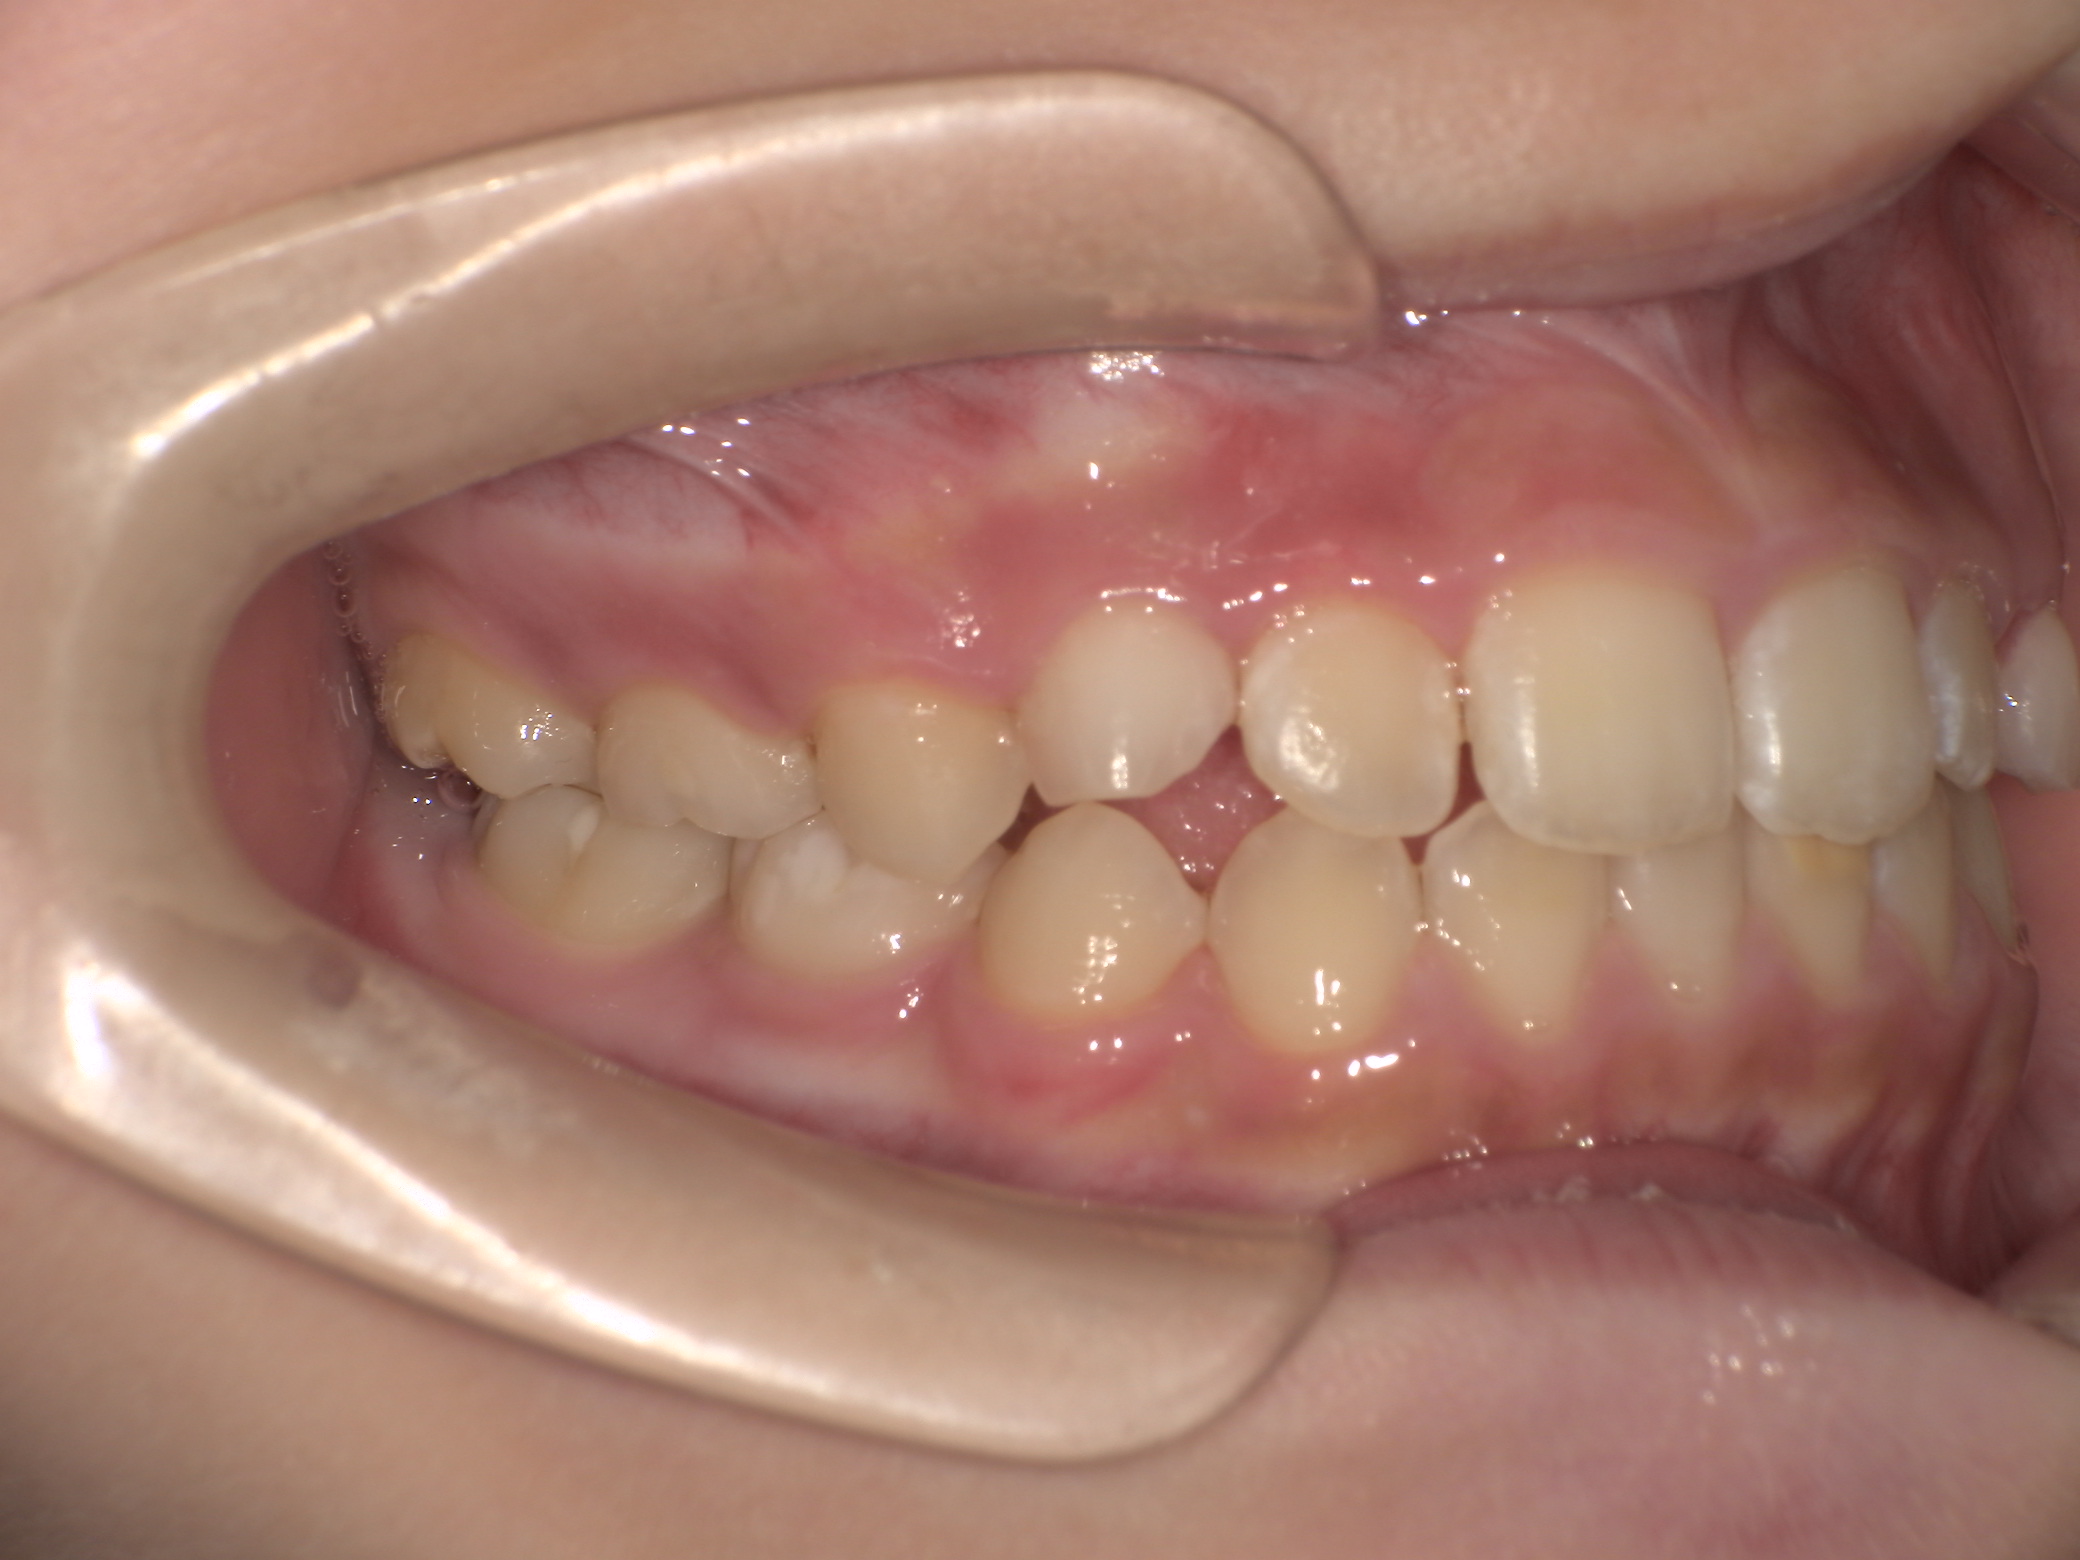

Before

治療開始前(9歳5か月)